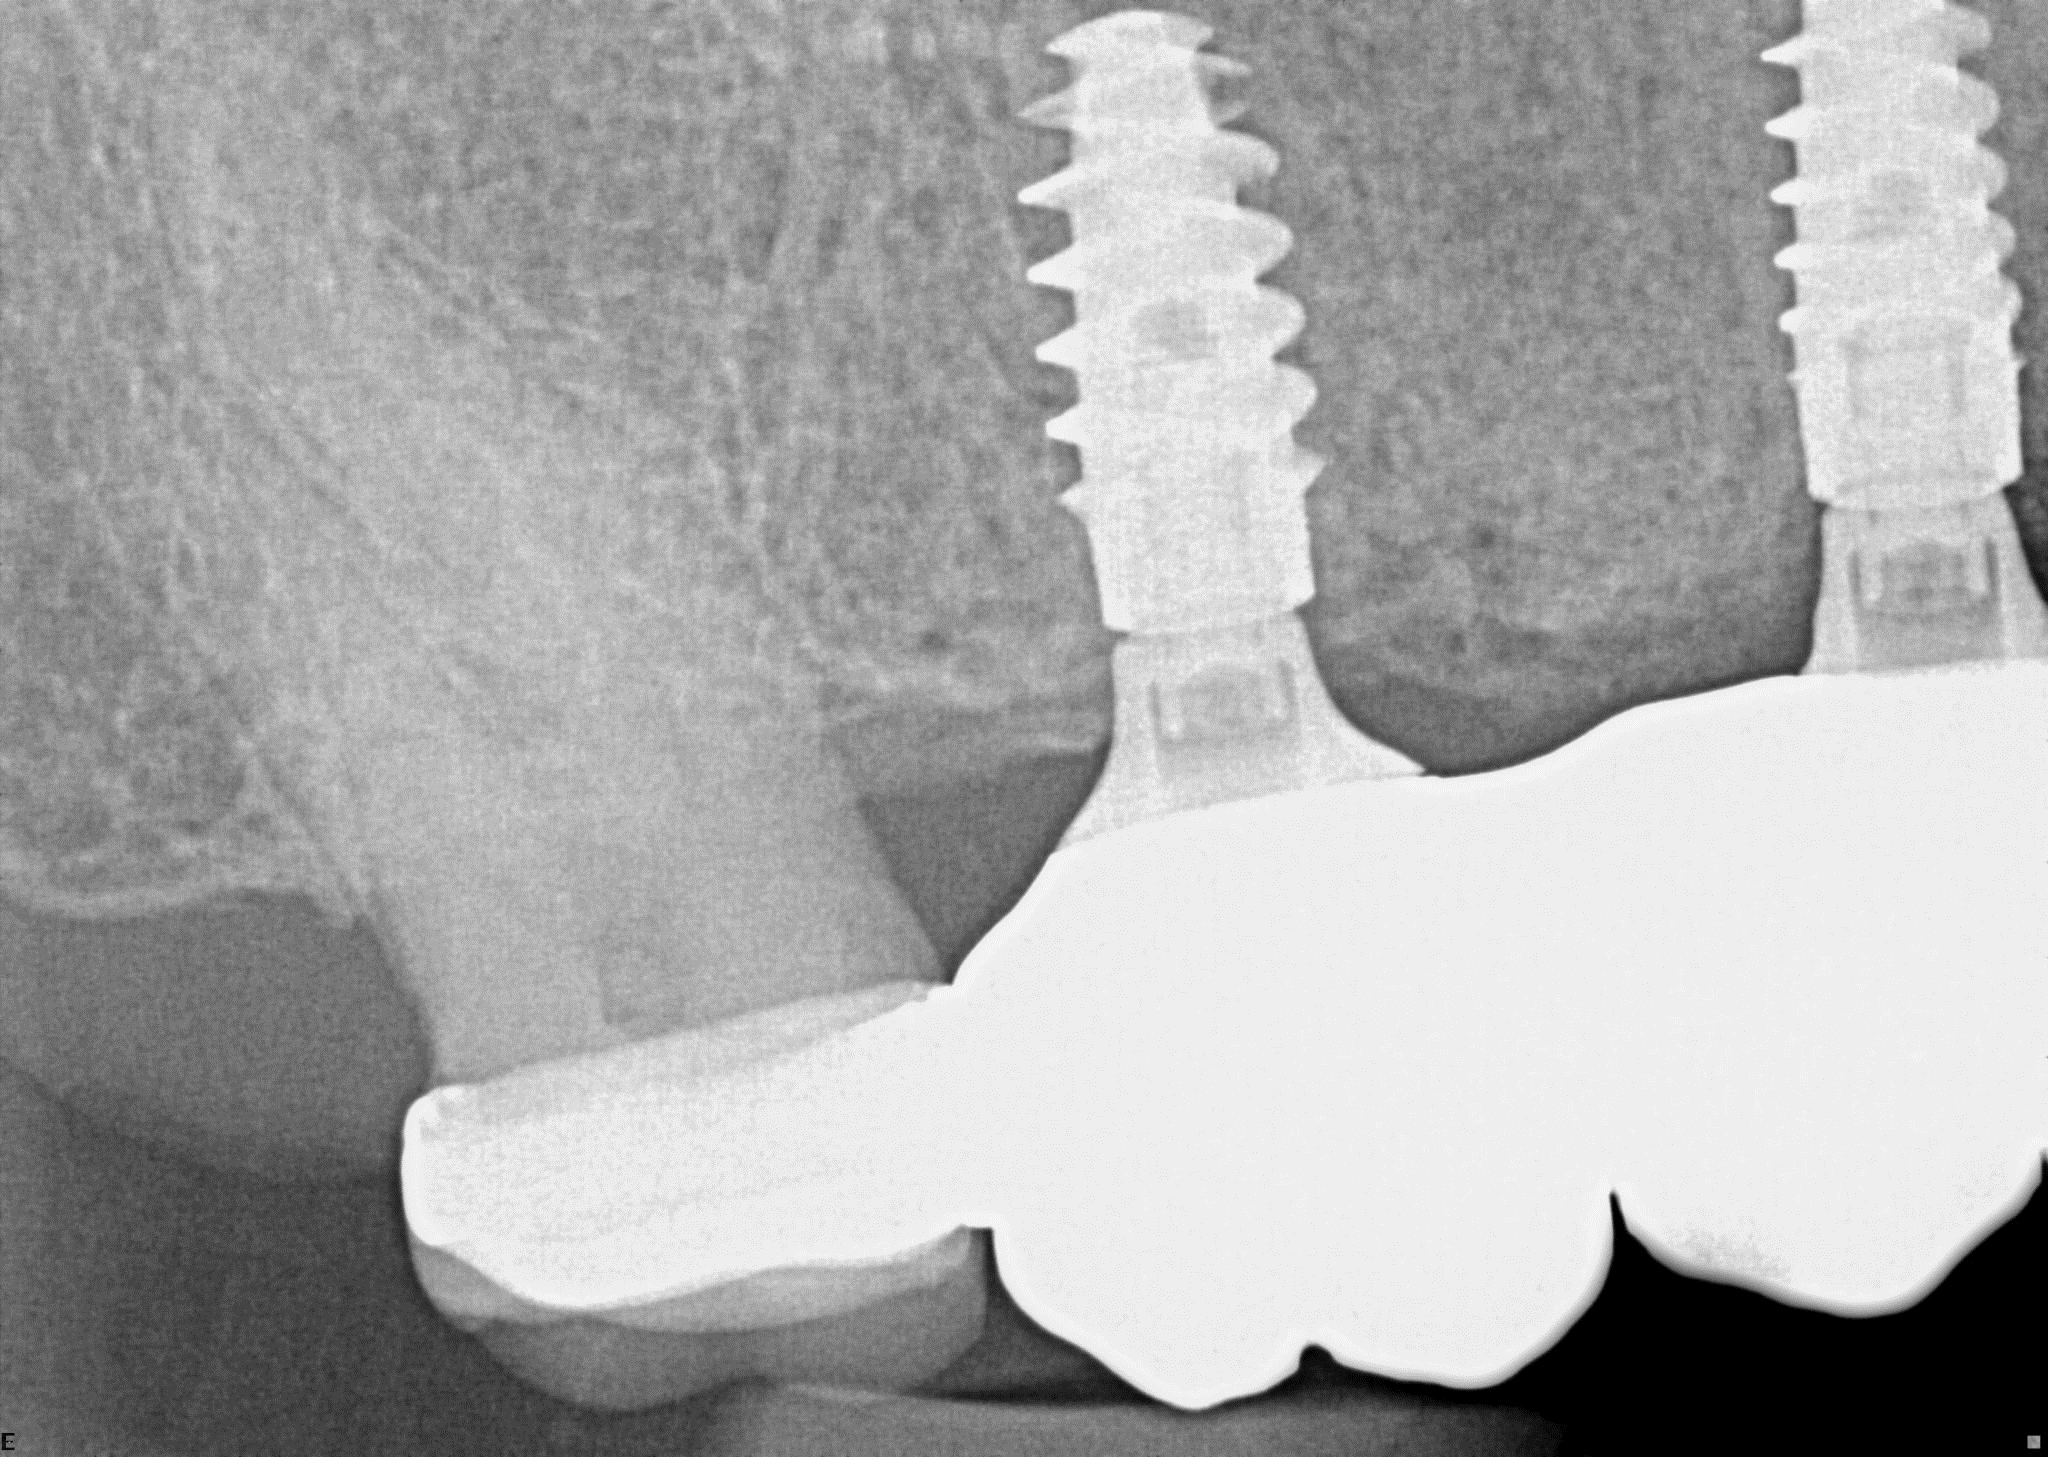

Tooth 4.8 is planned for extraction. Which radiographic findings suggest an increase in the degree of difficulty of the extraction?

13. (Select ONE OR MORE correct answers.)

Tooth 1.8 is planned for surgical extraction. Which radiographic findings suggest an increase in the degree of difficulty of the extraction?

Tooth 2.8 is planned for surgical extraction. Which radiographic findings suggest an increase in the degree of difficulty of the extraction?